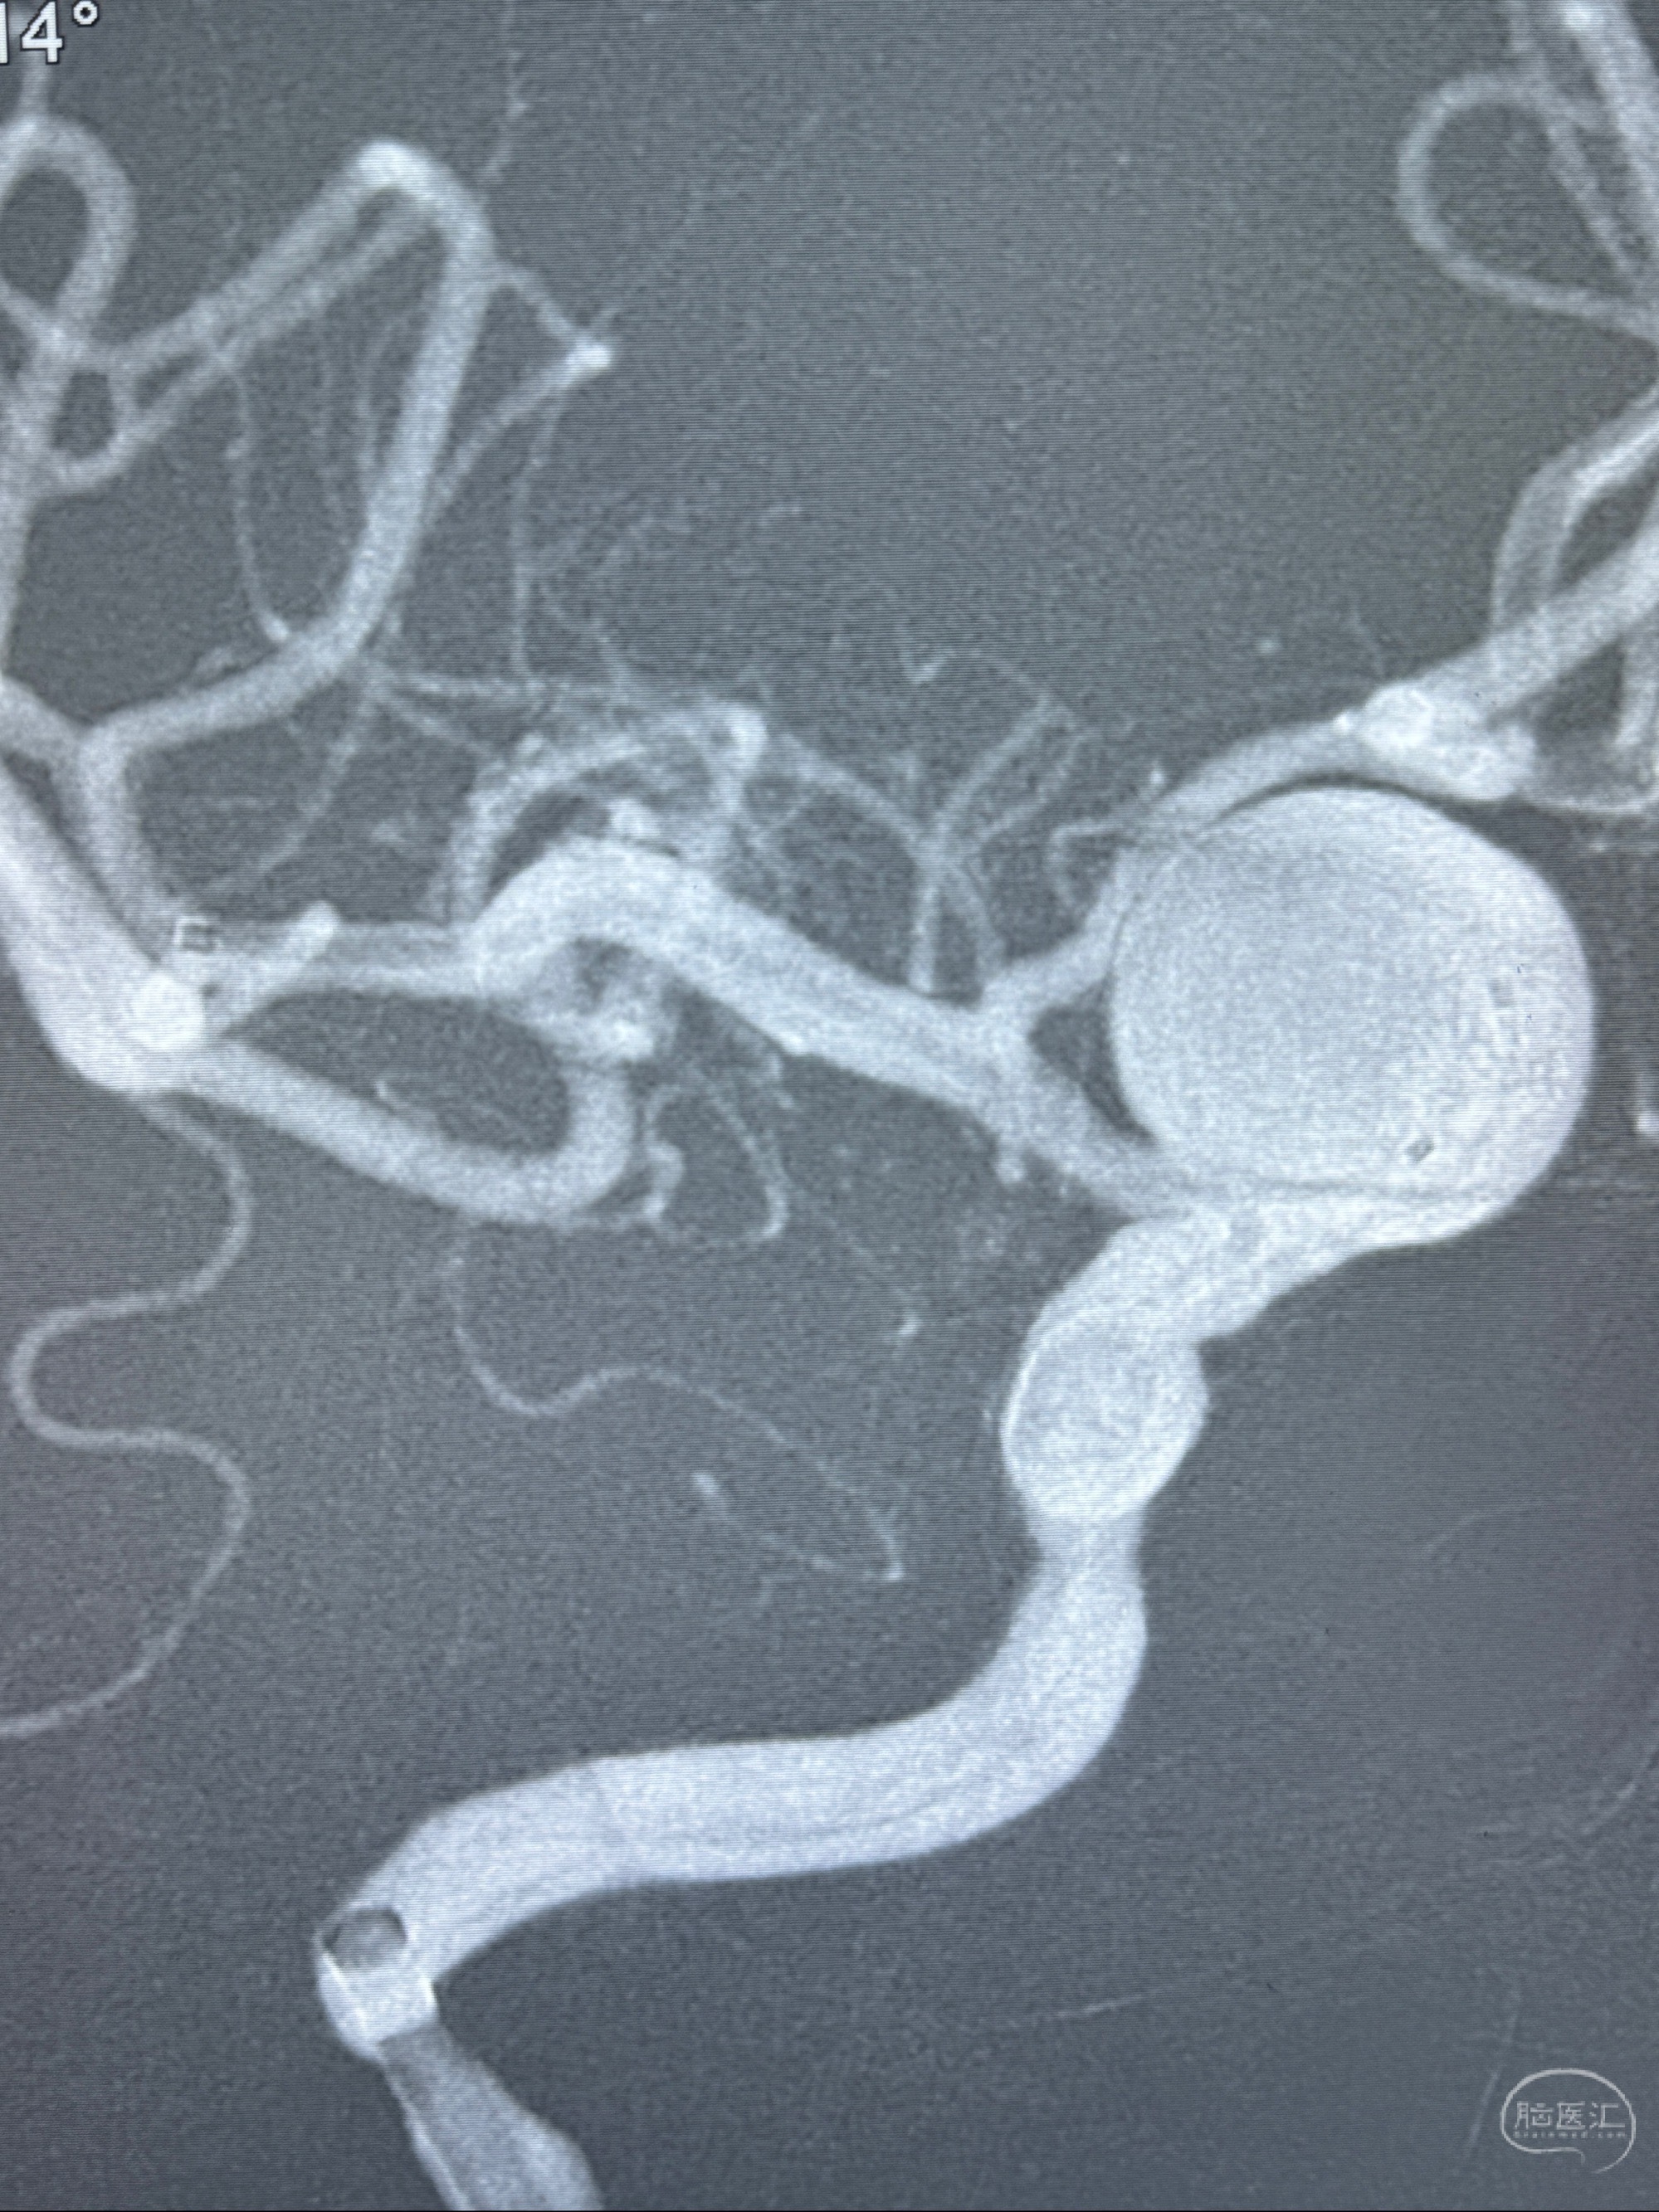

旋转3D展示动脉瘤局部的血管构筑

测量动脉瘤的大小:16*13.8*7.6mm大小,较原先变大,考虑双抗后瘤内血栓溶解可能

观察动脉瘤腔内的血流动力学情况